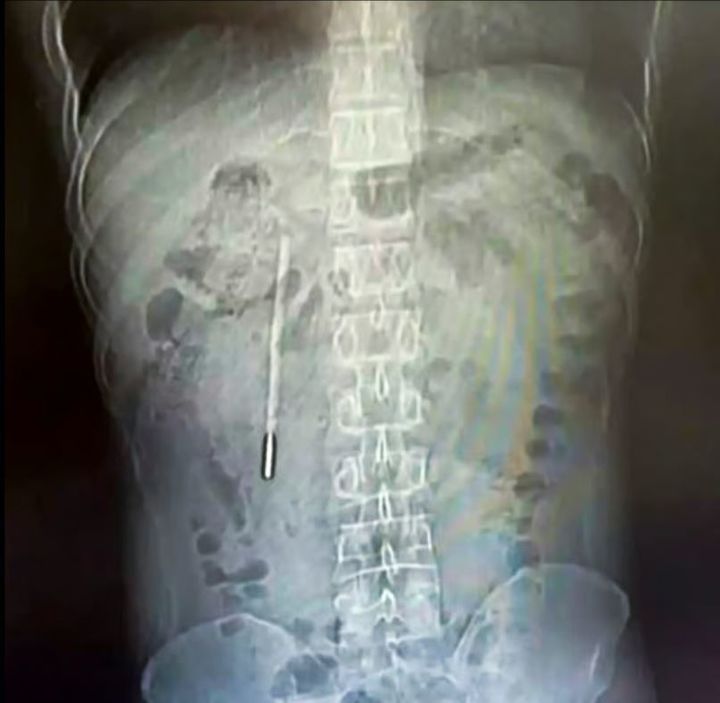

ワンさんの体内にあった水銀体温計を示すレントゲン画像。(写真=ウェイボー)

精密検査の結果、該当の物体は子供の頃に飲み込んだ水銀体温計であることが確認された。体温計は十二指腸の部分に引っかかったまま長期間留まっており、先端が腸壁に触れて穿孔や内出血につながる恐れのある危険な状態だったと伝えられた。

医療陣は内視鏡を通じて約20分で体温計を除去した。体温計は長い間、胆管の近くに位置していたが破損はしておらず、水銀の漏出も発生していなかった。ただし、外部の目盛りはほとんど消えかかっている状態だった。